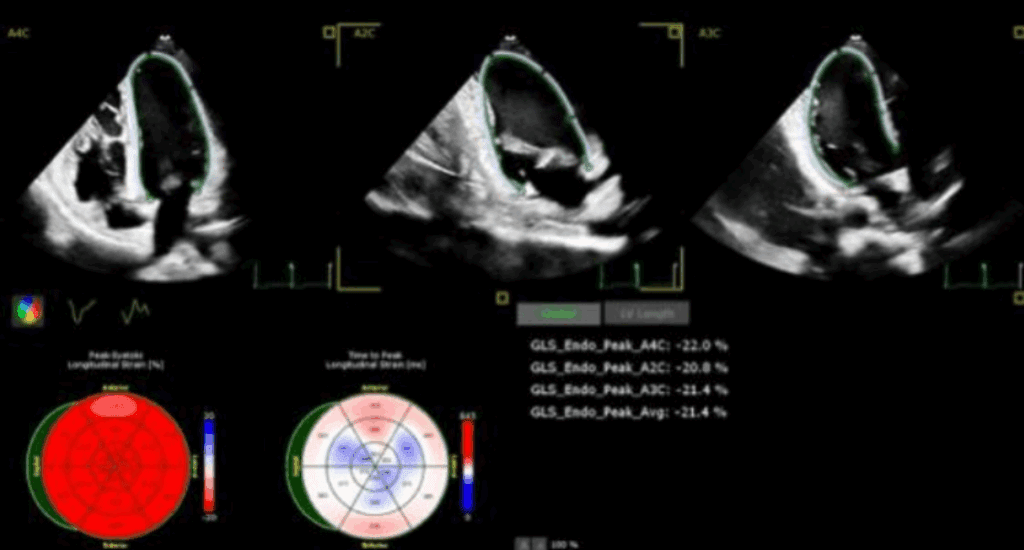

Odkształcenie mięśnia sercowego (strain) jest metodą szeroko wykorzystywaną w diagnostyce echokardiograficznej w grupie chorych z przerostem mięśnia lewej komory serca (ang. left ventricular – LV) o różnej etiologii. W tej grupie chorych standardowe przezklatkowe badanie echokardiograficzne (ang. transthoracic echocardiography – TTE) rozszerzone o pomiar odkształcenia lewej komory serca (ang. left ventricular strain – LV-GLS) ułatwia rozpoznanie, jak i pozwala na różnicowanie przyczyn przerostu LV.

W artykule przedstawiono przypadki kliniczne różnych pacjentów z chorobami układu sercowo-naczyniowego oraz przerostem mięśnia sercowego, u których pomiar odkształcenia (strain) LV istotnie ułatwia diagnostykę różnicową.